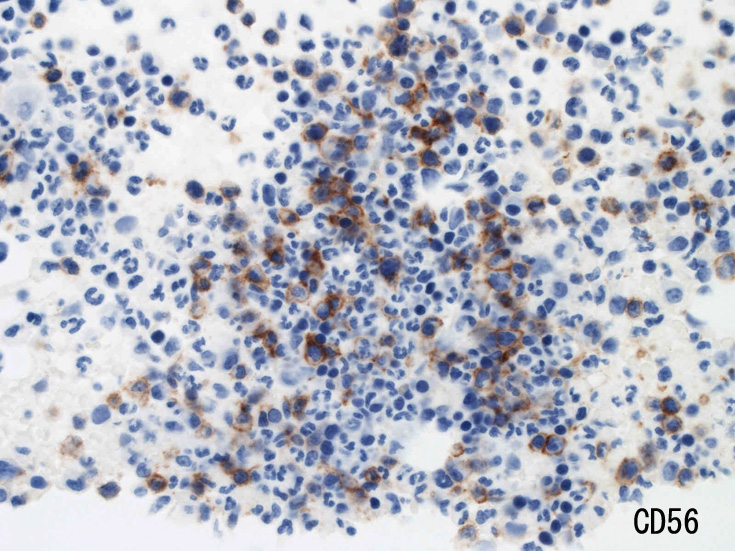

骨髄免疫染色およびISH

MG染色での大型異型細胞はCD56, CD30陽性。CD3は陰性を示す